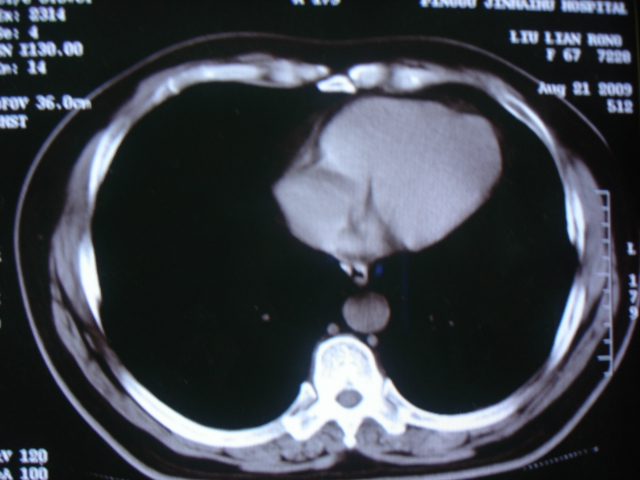

第三次ct2009.8.21